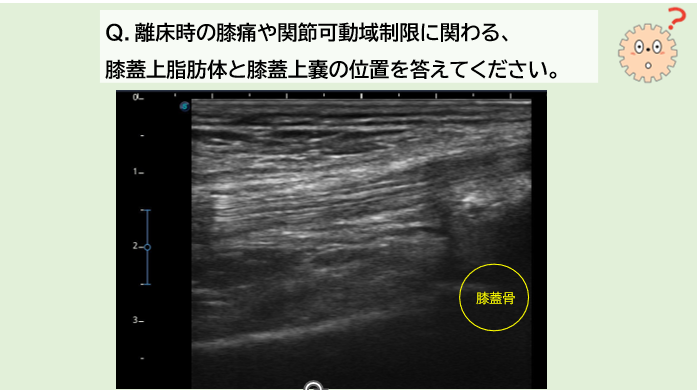

[解答例]